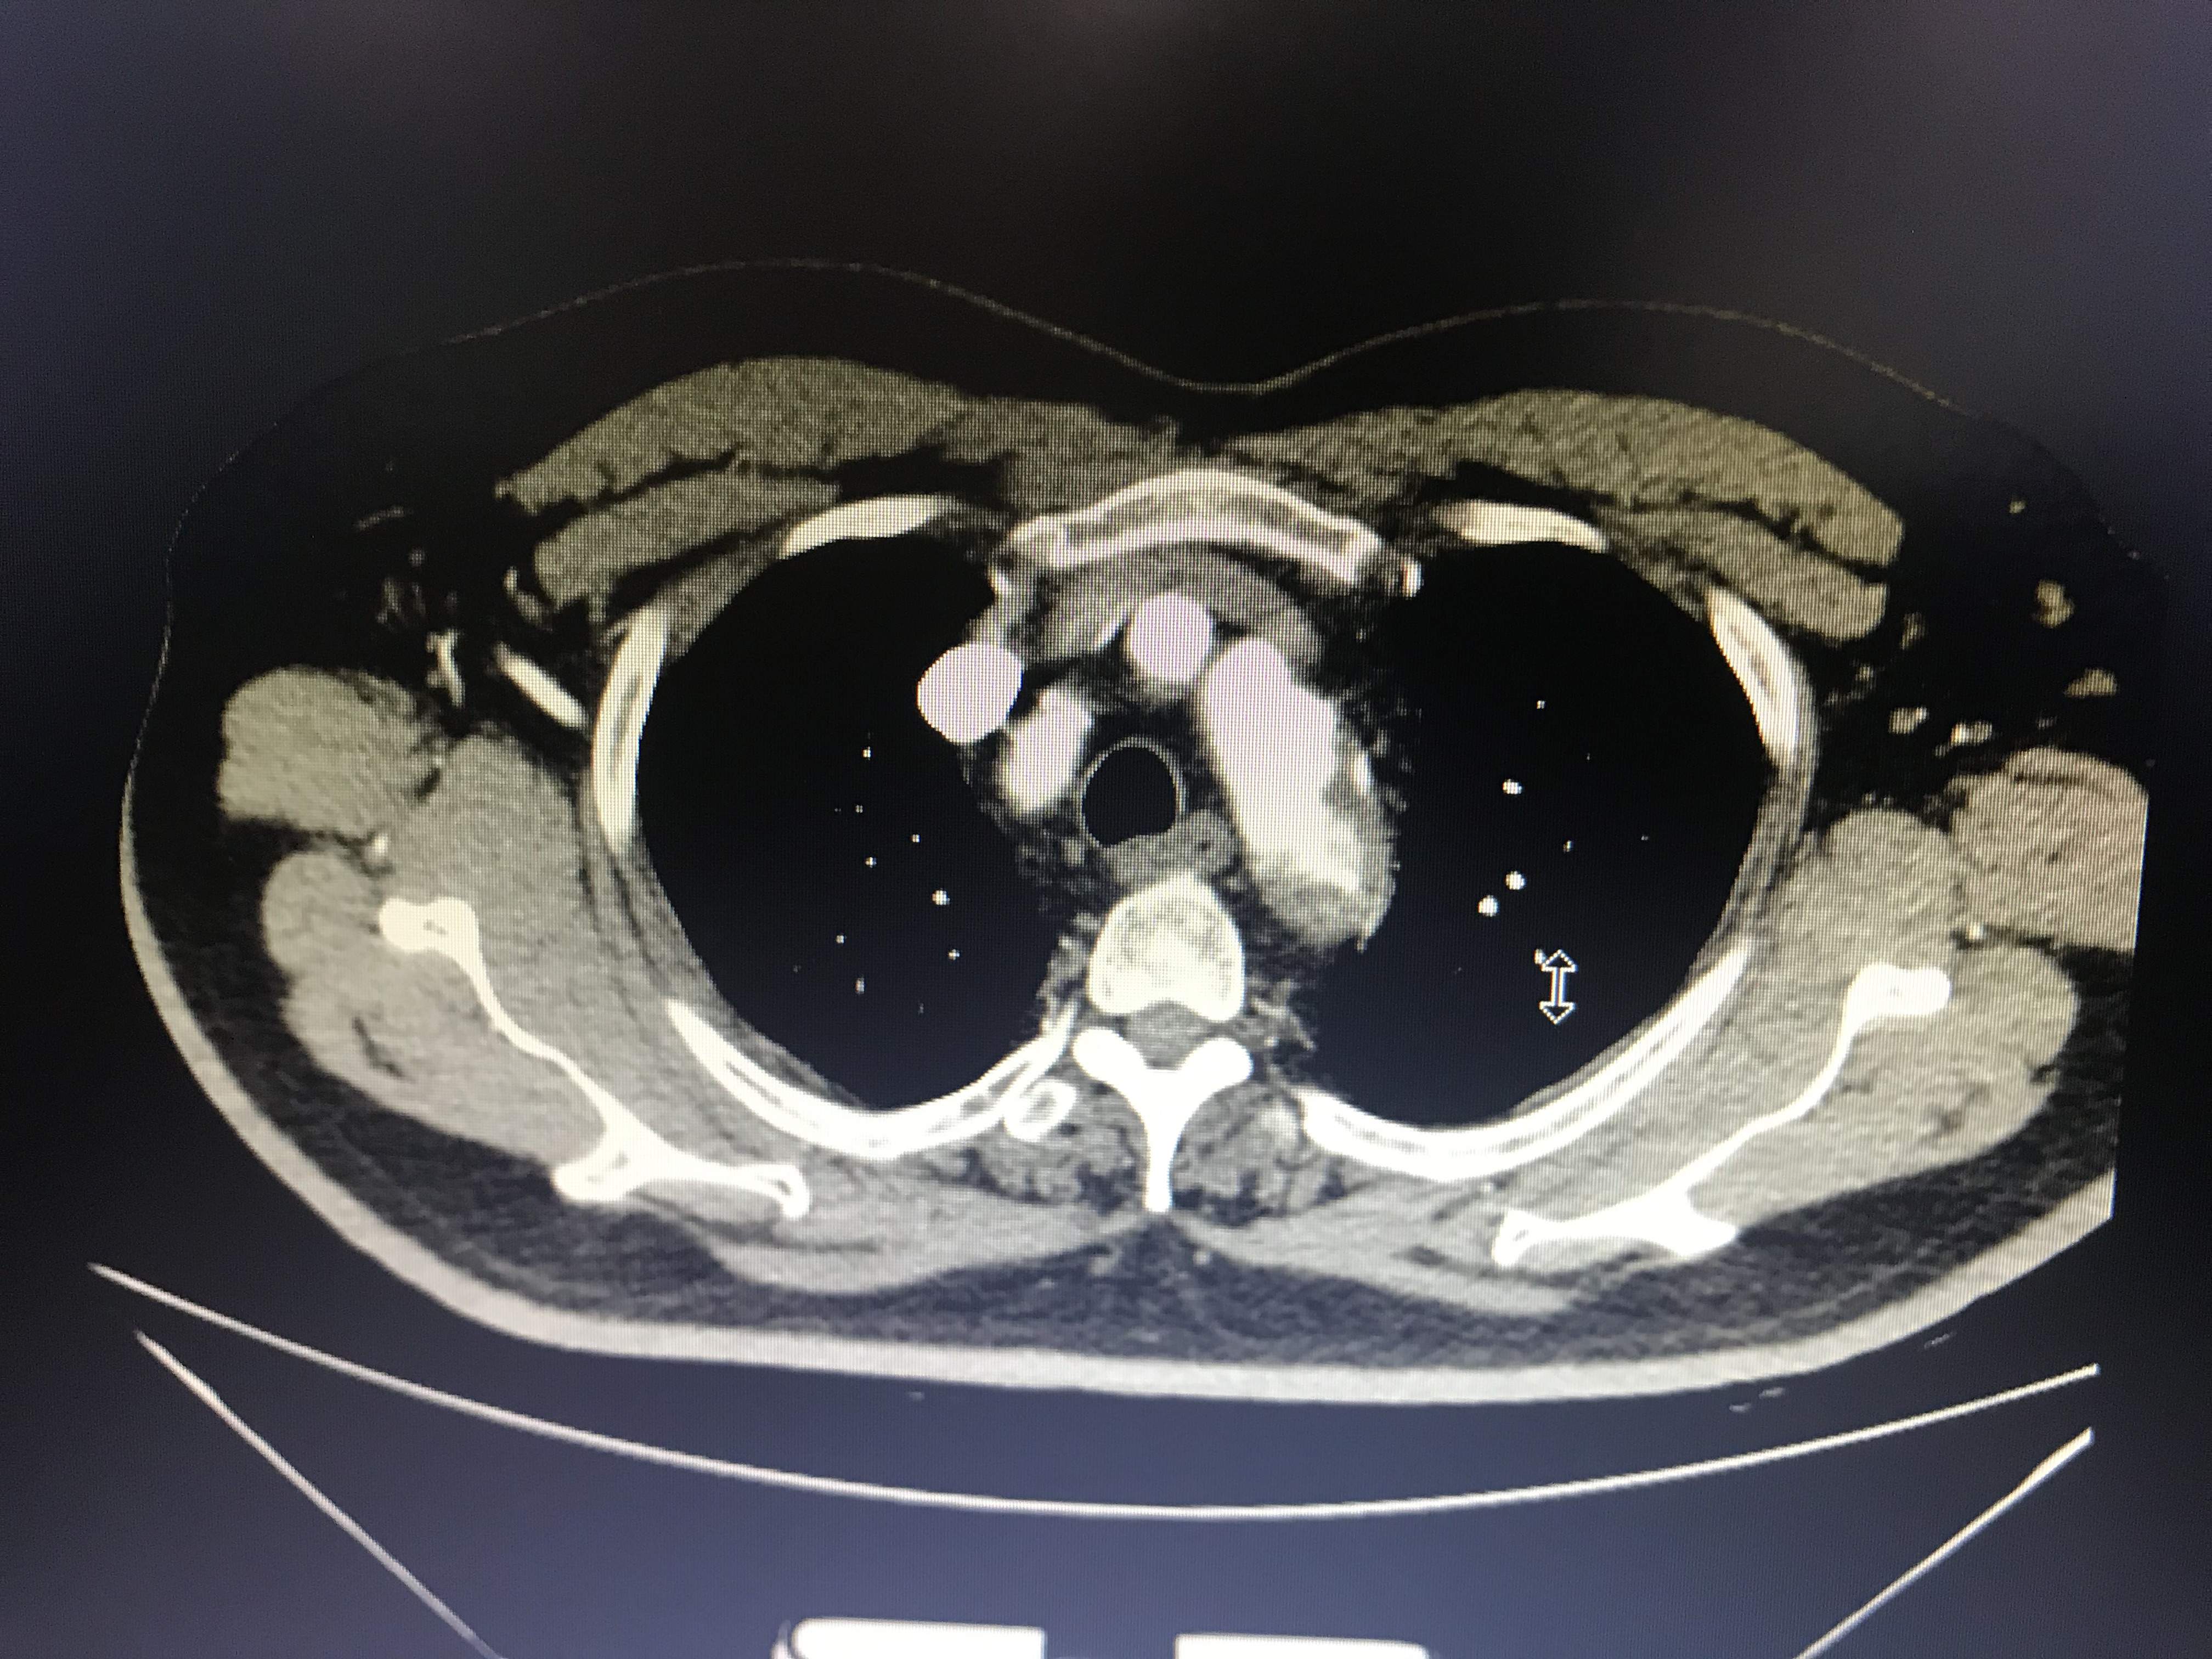

病人胸痛,这图像竟然不是主动脉溃疡?

大家帮我忙看看,到底是不是主动脉溃疡?